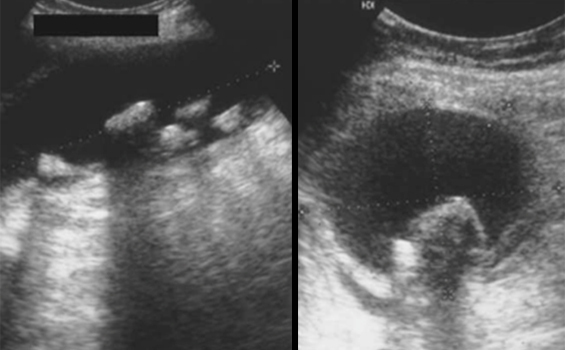

Il s’agit d’une image typique de cholécystite aiguë lithiasique sans signe de complication.